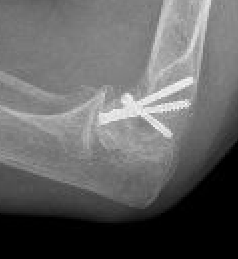

Capitellum fracture with radial head fracture

capcap

Capitellum fracture with radial head dislocation due to LCL injury